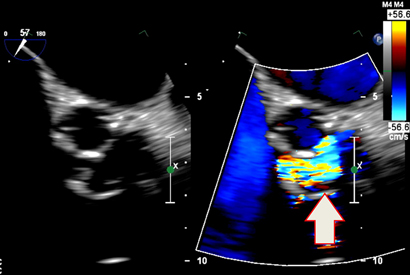

Transthoracic echocardiography showed severe prosthetic valve aortic regurgitation and thickening of the prosthetic valve leaflets with moderate aortic stenosis, with a maximum gradient of 96 mmHg and a mean gradient of 51 mmHg. Transoesophageal echocardiography confirmed severe transvalvular aortic regurgitation and thickened prosthetic valve leaflets, but no defined vegetations were present (Box 1).

The diagnosis of QFE is usually based on serological investigations, bacterial cultures and polymerase chain reaction (PCR) testing. Echocardiography may detect valvular vegetation in only 30% of cases.5